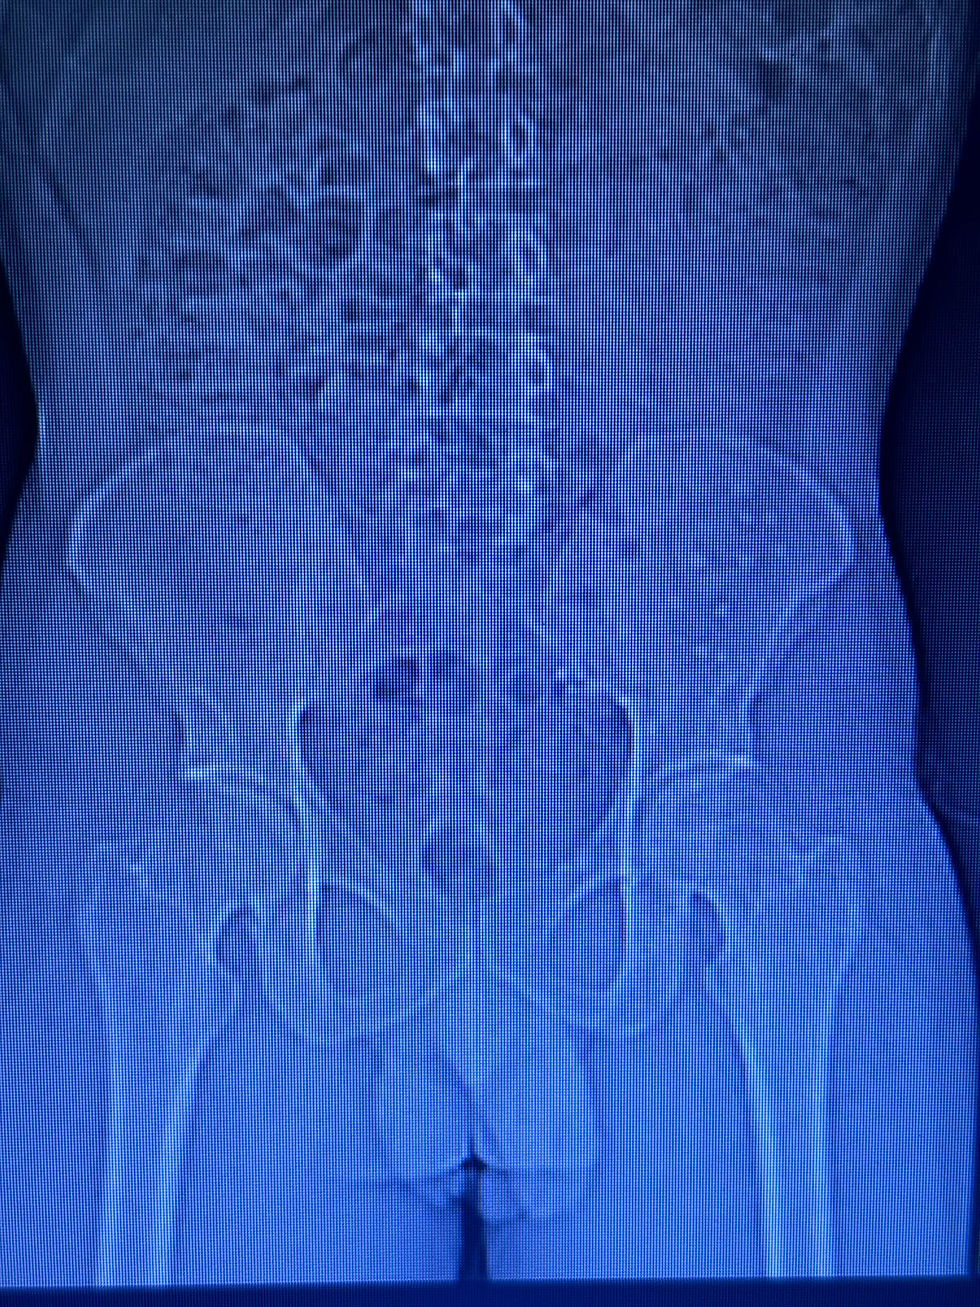

Rx com vários grampos de fixação.